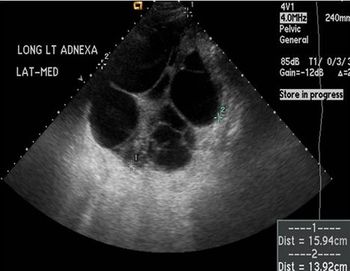

Ovarian Hyperstimulation SyndromeByVini Bapna, MDJuly 24th 2015With assisted reproduction widespread, all physicians, including primary care providers, should be familiar with presenting symptoms of OHSS.

Constant Dull Abdominal Pain in a 35-year-old WomanByVini Bapna, MDJuly 24th 2015The woman reported no other abdominal or gastrointestinal symptoms; menses were regular; a pregnancy test was negative. What next?